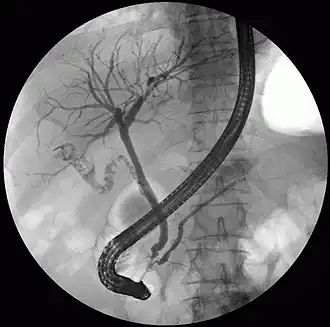

Fluoroscopic image taken during endoscopic retrograde cholangiopancreatography (ERCP). Multiple gallstones are present in the gallbladder and cystic duct. The common bile duct and pancreatic duct appear to be unobstructed.

On a different pathway, the physician may choose to proceed with ERCP before surgery. The benefit of ERCP is that it can be utilized not just to diagnose, but also to treat the problem. During ERCP the endoscopist may surgically widen the opening into the bile duct and remove the stone through that opening. ERCP, however, is an invasive procedure and has its own potential complications. Thus, if the suspicion is low, the physician may choose to confirm the diagnosis with MRCP, a non-invasive imaging technique, before proceeding with ERCP or surgery.